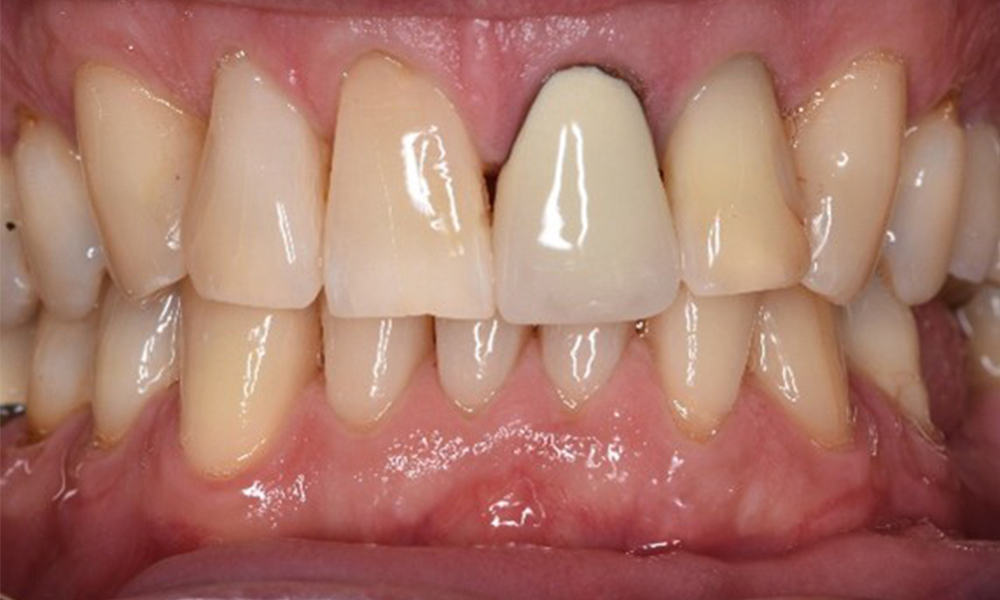

Die gesunde Patientin mit parodontaler Vorerkrankung

Die 68-jährige Patientin hat keine zahnmedizinisch relevanten allgemeingesundheitlichen Vorerkrankungen oder Medikation, auch aus dem Lebensstil ergibt sich kein besonderes Risiko. Die Patientin hat zwei Implantate (3. Quadrant, seit fünf Jahren) sowie eine parodontale Vorerkrankung (Parodontitis Stadium IV, Grad B) mit Zahnverlust. Derzeit zeigen sich stabile parodontale Verhältnisse. Für die Prophylaxesitzung ergeben sich vier Empfehlungen in den Bereichen Anamnese/Befund, Motivation/Instruktion, der Wahl der geeigneten Instrumente und für Resümee/Folgetermin. mehr Infos